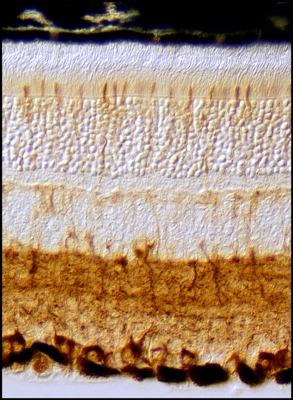

| Van Gogh's Skin by Carole Nicholas "Van Goghs Skin: The photograph under the microscope which inspired this piece surely is reminiscent of the now iconic Van Gogh's"The Starry Night". I tried to imitate in fabric and stitching Van Gogh's bursts of brushwork to create all the swirling movement he captured with paint. |

VanGogh's Skin

by Mark Hutchin, House Officer, Dermatology

This image shows a basal cell carcinoma, the most common form of skin cancer. The top portion shows the normal skin surface of a mouse, which stains red with this special stain (Masson trichrome stain). The blue is collagen, a strong fibrous substance that provides structural support for the skin. The appearance of human skin is very similar to this. At the bottom of the image, red staining tumor cells are seen. The yellow has been added for visual interest by the artist. By studying the development of tumors in the mouse, we hope to learn how to prevent the formation of similar tumors in humans. |